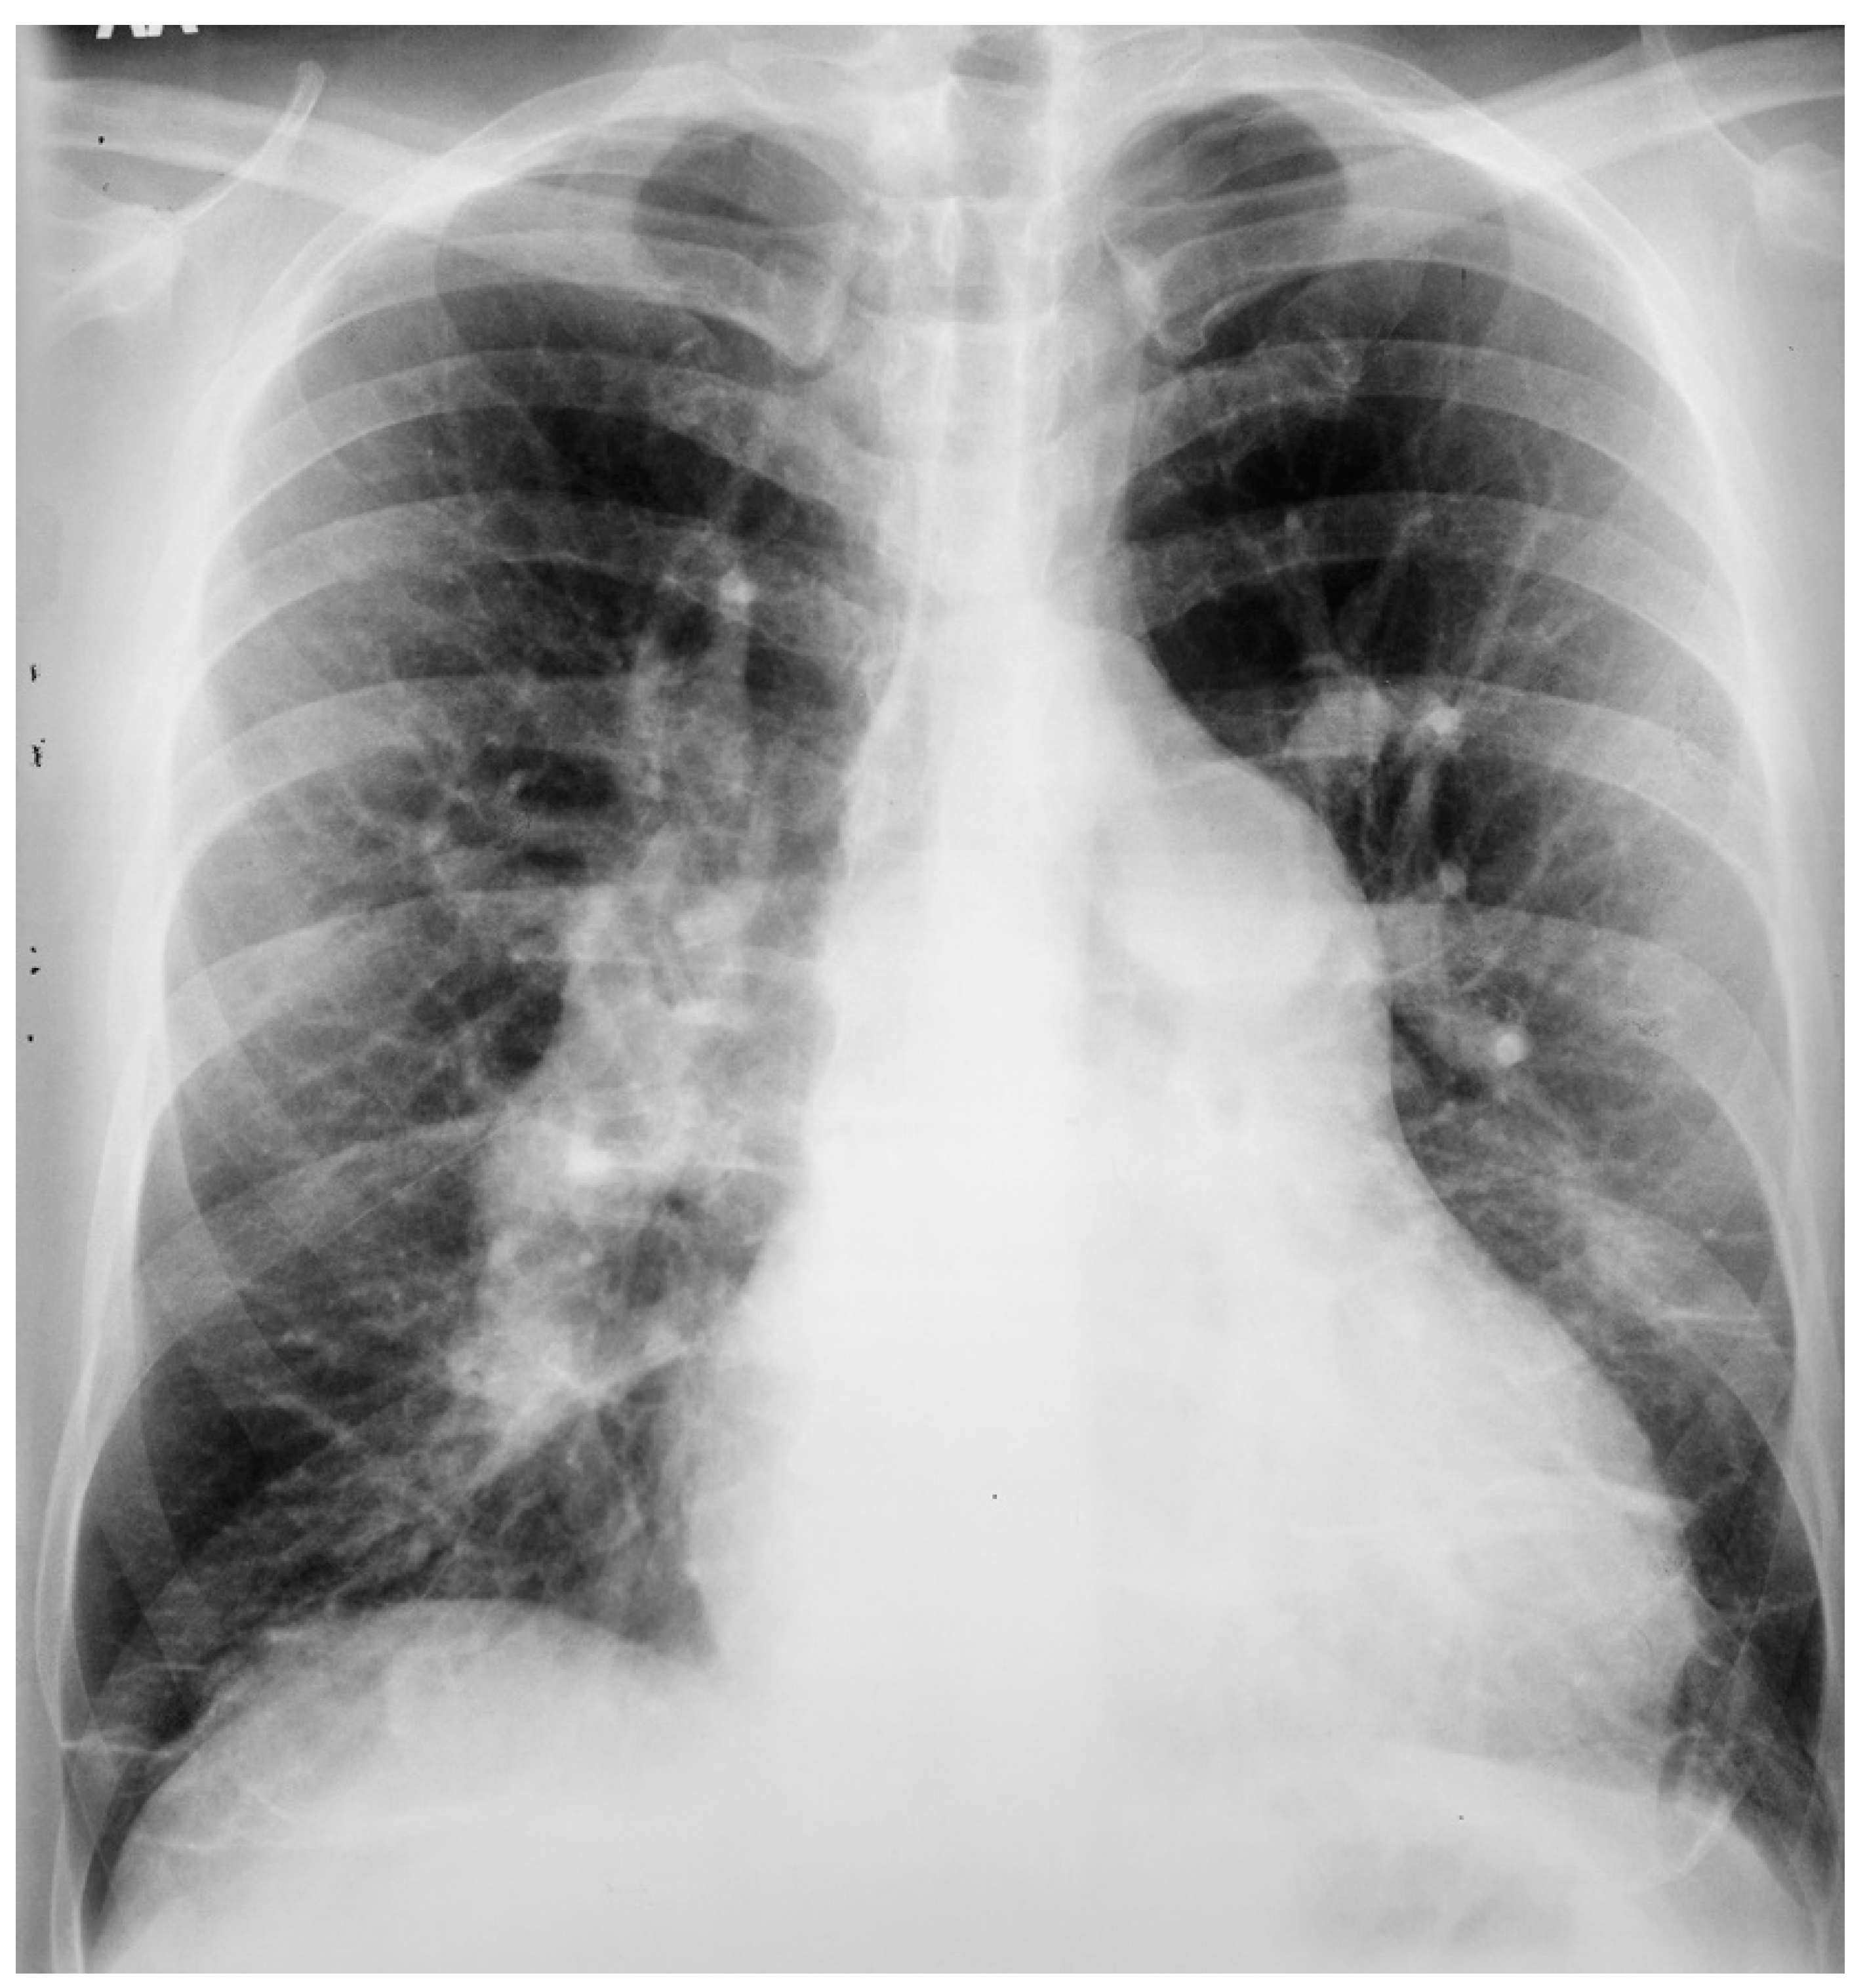

Figure 9.

Posteroanterior chest X-ray of sinus venosus atrial septal defect. This chest X-ray is of a 24-year-old female with a sinus venosus atrial septal defect and anomalous right upper pulmonary venous drainage to the superior vena cava. The image is well centered and there is a good inspiration. The cardiothoracic ratio is increased, the pulmonary artery segment is increased and the pulmonary vascularity is plethoric. Also note that there is a right-sided aortic arch (blue dots). This allows the enlarged pulmonary trunk to be better visualized because the thoracic aorta does not obscure it. Because she had dyspnea, fatigue and exercise intolerance she underwent surgical repair of the ASD and redirection of the right upper pulmonary vein to the left atrium. Her postoperative CXR showed decrease in C-T ratio and pulmonary vascularity. Her symptoms resolved.